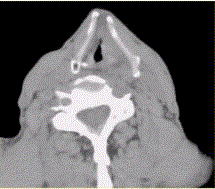

问题 患者男,60岁,声音嘶哑半年,CT表现如下图。 有关咽腔划分,正确的表述是

选项 A.分为鼻咽、口咽和喉咽 B.喉软骨包括甲状软骨、环状软骨和会厌软骨 C.喉腔可分为声门上区、声门区和声门下区 D.室带位于声带下方 E.双侧梨状窝可不对称 F.下咽癌包括梨状窝癌、环后癌及咽后壁癌

答案 ACEF